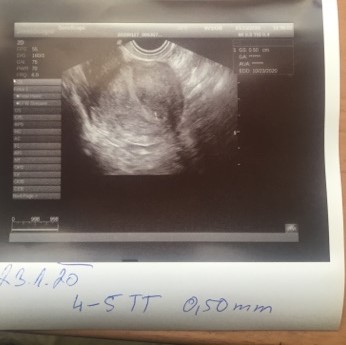

tak jsem.se vratila z gyn a nic tam zatim neni videt je moc brzo 14 dni po oplodneni tak me objednala za 4 tydny ze mi pak vystavi i prukazku😊tak snad tk vse dobre dopadne

jinak jsem 3+6 nrbo nejak tak takze je moc brzo i na gest.vacek

@packa17 toto je u mě 3+6tt 😀 a 10DPO,ale ano je ještě brzo aby něco bylo většinou v 3+6tt na UTZ 🙂